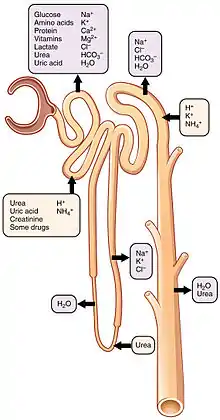

The four mechanisms used to create and process the filtrate (the result of which is to convert blood to urine) are filtration, reabsorption, secretion and excretion. Filtration or ultrafiltration occurs in the glomerulus and is largely passive: it is dependent on the intracapillary blood pressure. About one-fifth of the plasma is filtered as the blood passes through the glomerular capillaries; four-fifths continues into the peritubular capillaries. Normally the only components of the blood that are not filtered into Bowman's capsule are blood proteins, red blood cells, white blood cells and platelets. Over 150 liters of fluid enter the glomeruli of an adult every day: 99% of the water in that filtrate is reabsorbed. Reabsorption occurs in the renal tubules and is either passive, due to diffusion, or active, due to pumping against a concentration gradient. Secretion also occurs in the tubules and collecting duct and is active. Substances reabsorbed include: water, sodium chloride, glucose, amino acids, lactate, magnesium, calcium phosphate, uric acid, and bicarbonate. Substances secreted include urea, creatinine, potassium, hydrogen, and uric acid. Some of the hormones which signal the tubules to alter the reabsorption or secretion rate, and thereby maintain homeostasis, include (along with the substance affected) antidiuretic hormone (water), aldosterone (sodium, potassium), parathyroid hormone (calcium, phosphate), atrial natriuretic peptide (sodium) and brain natriuretic peptide (sodium). A countercurrent system in the renal medulla provides the mechanism for generating a hypertonic interstitium, which allows the recovery of solute-free water from within the nephron and returning it to the venous vasculature when appropriate.

The proximal tubule as a part of the nephron can be divided into an initial convoluted portion and a following straight (descending) portion.[11] Fluid in the filtrate entering the proximal convoluted tubule is reabsorbed into the peritubular capillaries, including 80% of glucose, more than half of the filtered salt, water and all filtered organic solutes (primarily glucose and amino acids).[4]: 400–401

The loop of Henle is a U-shaped tube that extends from the proximal tubule. It consists of a descending limb and an ascending limb. It begins in the cortex, receiving filtrate from the proximal convoluted tubule, extends into the medulla as the descending limb, and then returns to the cortex as the ascending limb to empty into the distal convoluted tubule. The primary role of the loop of Henle is to enable an organism to produce concentrated urine, not by increasing the tubular concentration, but by rendering the interstitial fluid hypertonic.[1]: 67

Considerable differences aid in distinguishing the descending and ascending limbs of the loop of Henle. The descending limb is permeable to water and noticeably less permeable to salt, and thus only indirectly contributes to the concentration of the interstitium. As the filtrate descends deeper into the hypertonic interstitium of the renal medulla, water flows freely out of the descending limb by osmosis until the tonicity of the filtrate and interstitium equilibrate. The hypertonicity of the medulla (and therefore concentration of urine) is determined in part by the size of the loops of Henle.[1]: 76

Unlike the descending limb, the thick ascending limb is impermeable to water, a critical feature of the countercurrent exchange mechanism employed by the loop. The ascending limb actively pumps sodium out of the filtrate, generating the hypertonic interstitium that drives countercurrent exchange. In passing through the ascending limb, the filtrate grows hypotonic since it has lost much of its sodium content. This hypotonic filtrate is passed to the distal convoluted tubule in the renal cortex.[1]: 72

The distal convoluted tubule has a different structure and function to that of the proximal convoluted tubule. Cells lining the tubule have numerous mitochondria to produce enough energy (ATP) for active transport to take place. Much of the ion transport taking place in the distal convoluted tubule is regulated by the endocrine system. In the presence of parathyroid hormone, the distal convoluted tubule reabsorbs more calcium and secretes more phosphate. When aldosterone is present, more sodium is reabsorbed and more potassium secreted. Ammonia is also absorbed during the selective reabsorption. Atrial natriuretic peptide causes the distal convoluted tubule to secrete more sodium.

Collecting duct system

Each distal convoluted tubule delivers its filtrate to a system of collecting ducts, the first segment of which is the connecting tubule. The collecting duct system begins in the renal cortex and extends deep into the medulla. As the urine travels down the collecting duct system, it passes by the medullary interstitium which has a high sodium concentration as a result of the loop of Henle's countercurrent multiplier system.[1]: 67

Though the collecting duct is normally impermeable to water, it becomes permeable in the presence of antidiuretic hormone (ADH). ADH affects the function of aquaporins, resulting in the reabsorption of water molecules as it passes through the collecting duct. Aquaporins are membrane proteins that selectively conduct water molecules while preventing the passage of ions and other solutes. As much as three-quarters of the water from urine can be reabsorbed as it leaves the collecting duct by osmosis. Thus the levels of ADH determine whether urine will be concentrated or diluted. An increase in ADH is an indication of dehydration, while water sufficiency results in a decrease in ADH allowing for diluted urine.[4]: 406

Lower portions of the collecting organ are also permeable to urea, allowing some of it to enter the medulla, thus maintaining its high concentration (which is very important for the nephron).[1]: 73–74